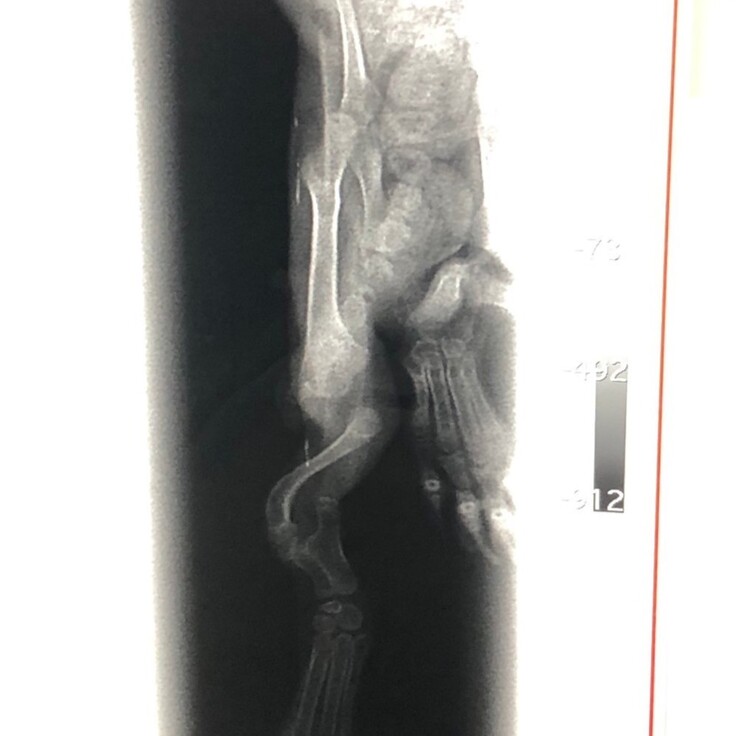

よく見ると足をぶらぶらさせていて、足が不自由なようでした。

足を引きずりながら移動する様子を見て、お外で暮らすことはできないと思いました。

2本あるはずの骨が1本しかない

健康状態のチェックや駆虫で通院するうちに、両後脚に通常あるはずの骨が無い箇所があり、

生まれつき重度の変形があるとわかりました。